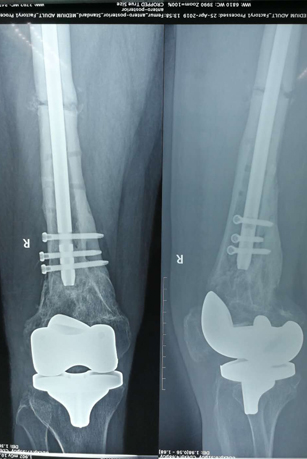

术前影像

在手术之前,首先做股骨全长薄层扫描CT,将患者股骨影像及数据搜集并记录下来,通过3D打印技术制作出一个1:1比例的股骨“复制品”,它的直径、长短、髓腔形态都与患者真实情况完全相符,甚至患者骨骼上每一块凹陷与凸起,每一点纹理和痕迹都呈现得一清二楚。然后通过在体外对模型进行模拟手术操作,准确制订出了髓内钉的入针点、长度、直径,精确计划出远端锁钉准确位置。手术时,按着术前的设计顺利完成了手术,大大缩短了手术时间,减少了对患者的创伤。术后影像骨折解剖复位,锁钉位置精准无误,术后患者顺利康复。

术后影像